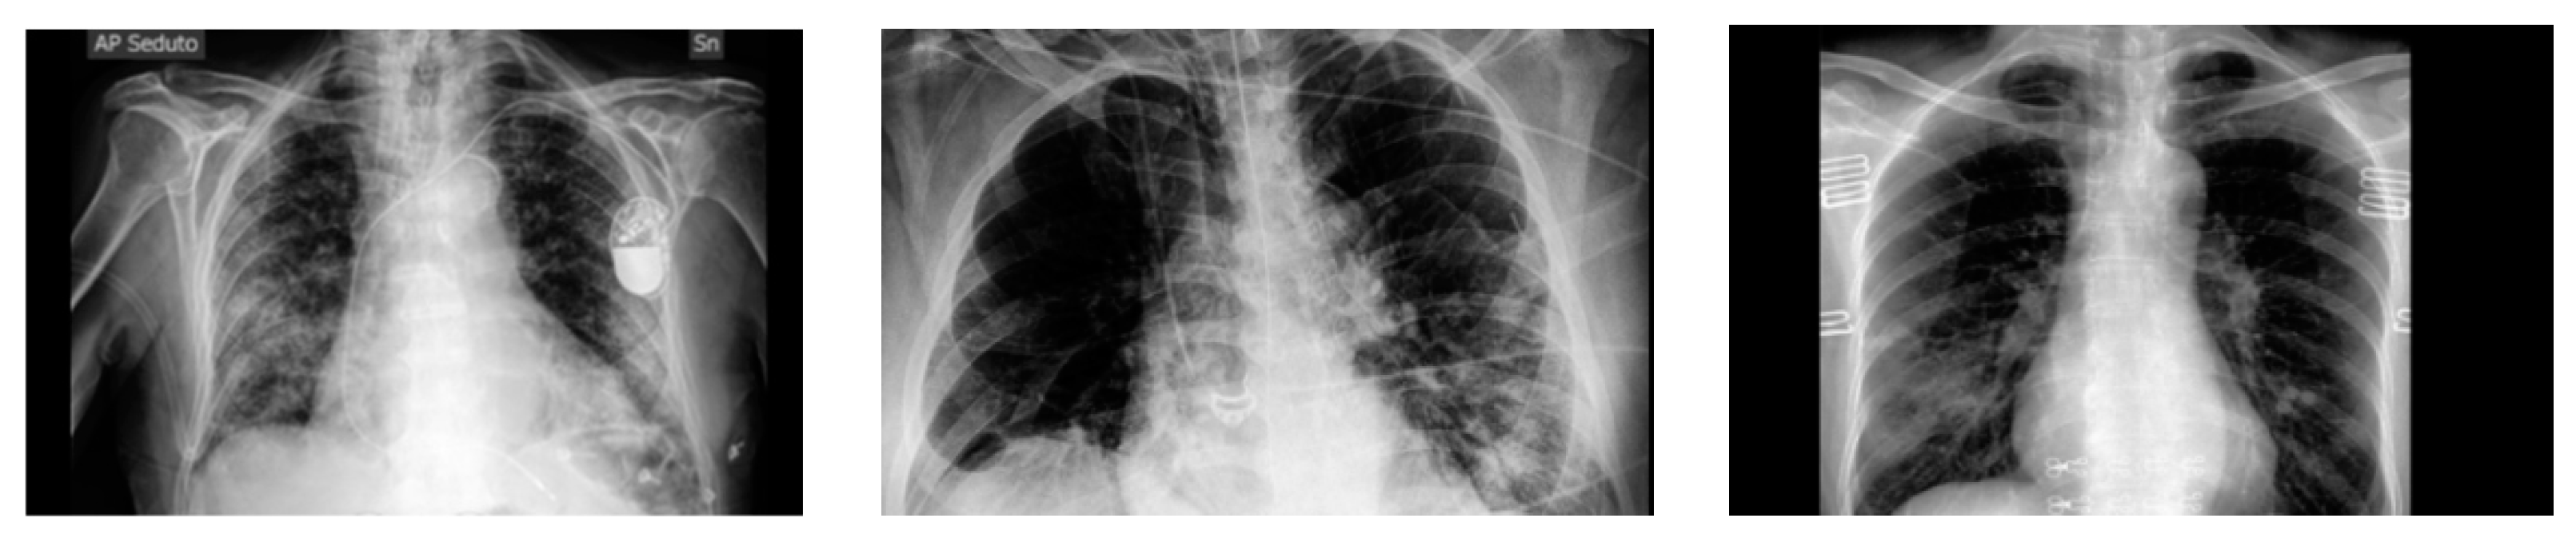

Figure 1. Data sample.

Preprints 139416 g001